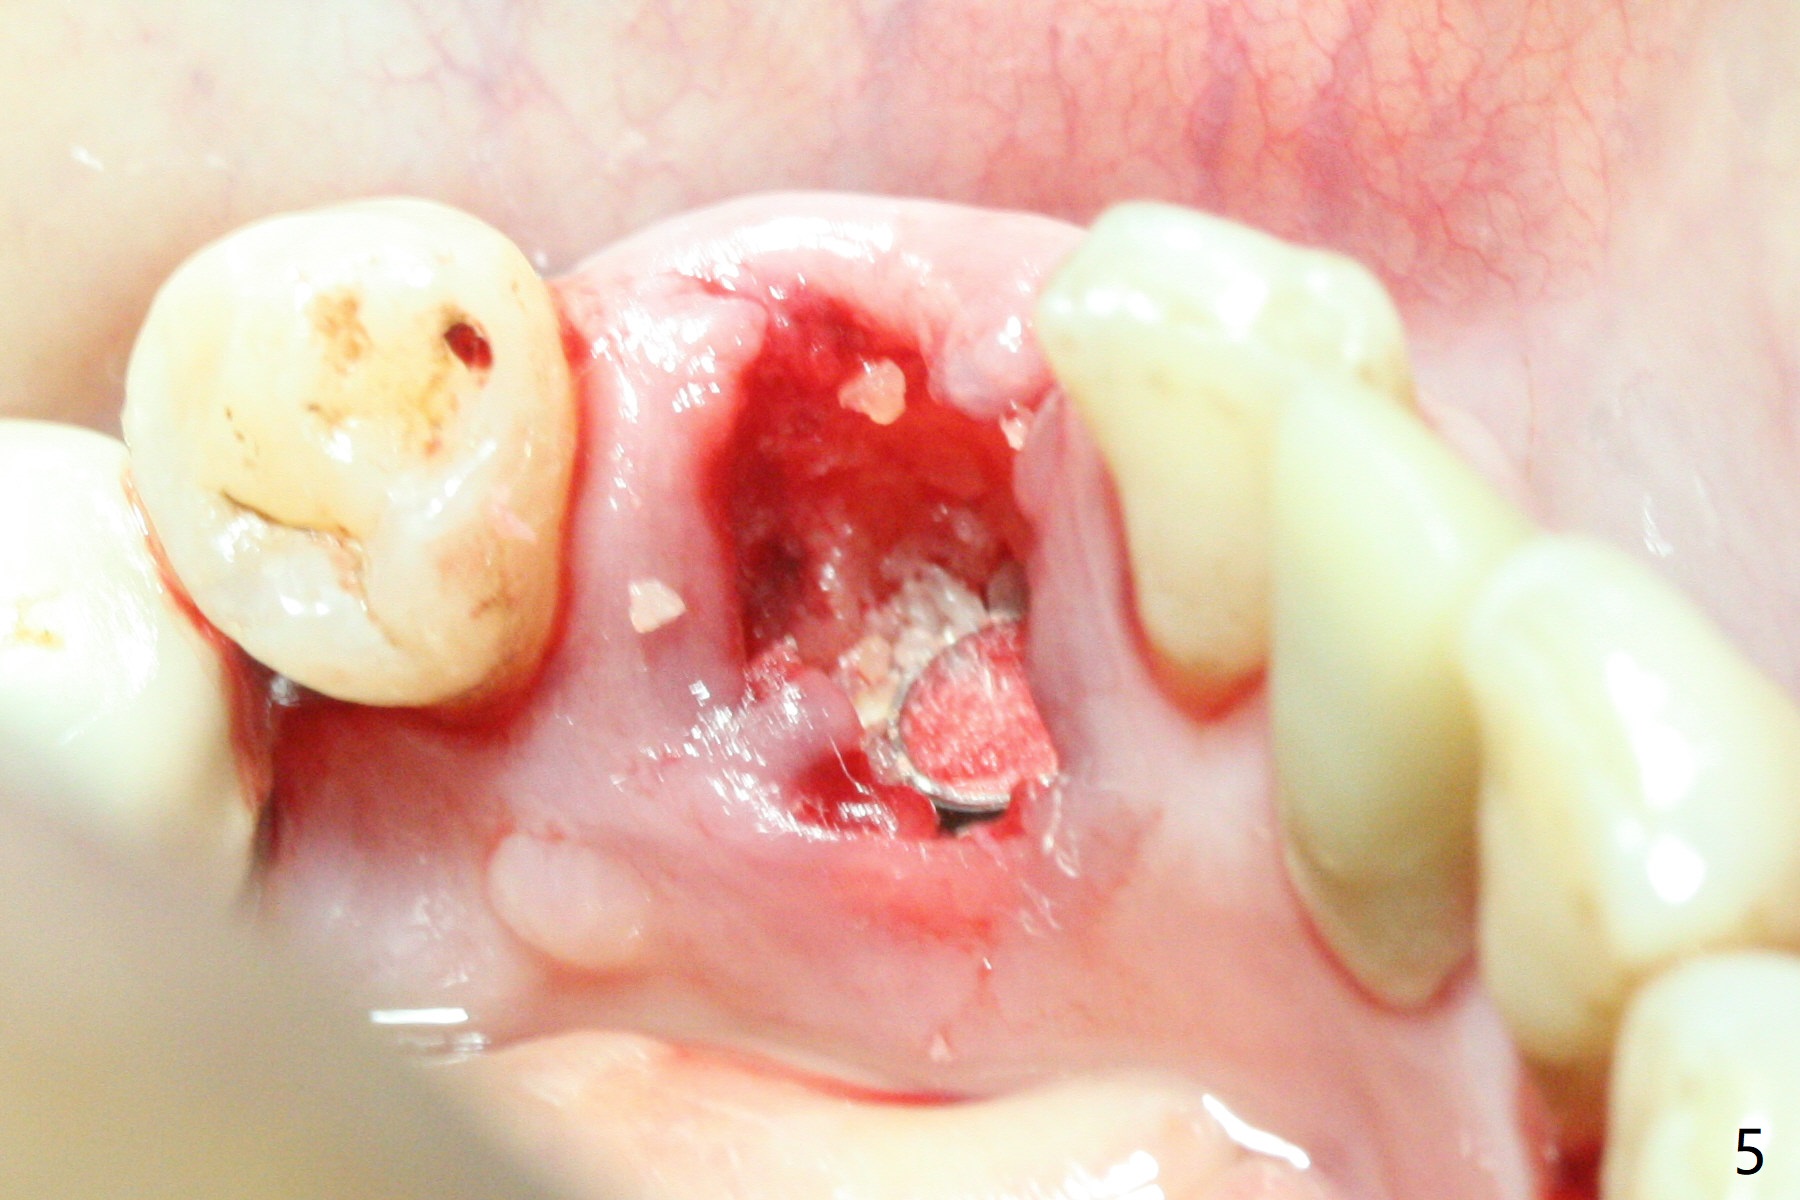

There is a fistula buccal to the apex of the tooth #23 preoperatively (Fig.1), which is related to loss of the buccal plate of the socket of #23. Therefore an implant is placed mainly in the socket of #22 (Fig.3). The lingual (Fig.2 L) gingiva appears to have more extensive inflammation. After extraction, the lingual (Fig.3 L) gingival margin is significantly lower than the buccal one. The lingual crest is ~ 4 mm lower than the buccal one. A 3.8x10 mm dummy implant is placed tentatively with an apical space (Fig.4). When a same dimension definitive implant is placed with 40 Ncm, it is 2 mm below the lingual gingival margin, whereas 6-7 mm below the buccal one (Fig.5). Vanilla graft is placed before placement of a 5.5x4(5) mm abutment (Fig.6,7). There is a 2-3 mm lingual (L) gap to be filled with the allograft secondarily to prevent periimplantitis (Fig.7). Later the abutment is changed to a longer and smaller one (Fig.8) with more of the allograft (*). After trimming of the abutment (Fig.9 (*: papilla between the fused teeth)), an immediate provisional is fabricated to close the socket (Fig.10, similar to Fig.1). The majority of the bone graft seems to be in place 8 months postop (Fig.12). The implant appears to have been placed buccal, consistent with the thin and slightly erythematous buccal gingiva (Fig.13). The ridge completely regenerates 2 years post cementation (Fig.14).